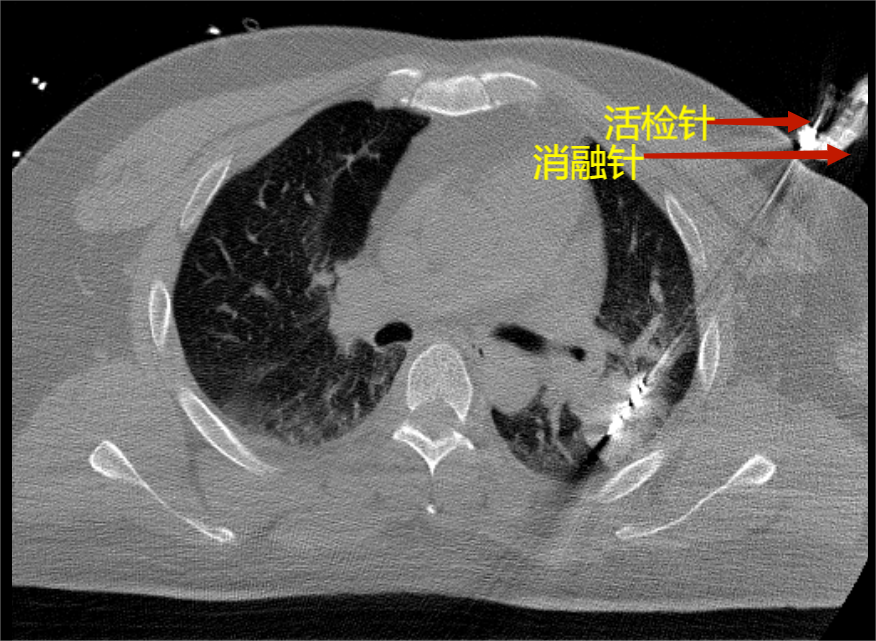

CT引導(dǎo)下肺腫瘤穿刺消融術(shù)是否可以同時(shí)穿刺活檢取得病理?

是的,CT引導(dǎo)下肺腫瘤穿刺消融術(shù)通??梢酝瑫r(shí)進(jìn)行穿刺活檢以獲取病理標(biāo)本。這種做法可以提供更詳細(xì)的腫瘤類型和病理特征信息,有助于確診和指導(dǎo)后續(xù)治療。?在進(jìn)行CT引導(dǎo)下肺腫瘤穿刺消融術(shù)時(shí),醫(yī)生通常會(huì)在穿刺過(guò)程中采取穿刺活檢的方法。通過(guò)在穿刺引導(dǎo)針內(nèi)置入活檢槍,醫(yī)生可以在穿刺過(guò)程中取得腫瘤組織的樣本。這些樣本可以送往實(shí)驗(yàn)室進(jìn)行病理學(xué)檢查,以確定腫瘤的類型、分級(jí)和其他分子病理特征等。?穿刺活檢在CT引導(dǎo)下肺腫瘤穿刺消融術(shù)中的實(shí)施需要醫(yī)生具備較高的相關(guān)專業(yè)技能和經(jīng)驗(yàn),以確保準(zhǔn)確獲取病理標(biāo)本同時(shí)最小化并發(fā)癥的風(fēng)險(xiǎn),通常穿刺活檢會(huì)增加氣胸和咯血的風(fēng)險(xiǎn),此外也有病理假陰性的風(fēng)險(xiǎn)。因此,穿刺活檢的可行性和適用性可能會(huì)因患者的具體情況和腫瘤特征而有所不同。在決定是否進(jìn)行穿刺活檢時(shí),醫(yī)生會(huì)綜合考慮多種因素,如腫瘤的位置、大小、形態(tài)以及患者的整體情況等再進(jìn)行選擇。

肺腫瘤微波消融同步肺穿刺活檢治療晚期肺癌

CT經(jīng)皮肺穿刺活檢屬于有創(chuàng)性檢查,在CT的引導(dǎo)下,局部麻醉后,使用穿刺針穿過(guò)胸膜和肺,進(jìn)入到腫物或結(jié)節(jié),取到腫瘤組織。用于病理診斷,還可以做腫瘤基因檢測(cè)指導(dǎo)靶向藥物等治療。肺穿刺活檢的常見(jiàn)風(fēng)險(xiǎn):氣胸:因?yàn)槭侵苯哟┐谭谓M織,所以可能會(huì)引起氣胸,但大多數(shù)這種穿刺引起的氣胸可以保守治療自行好轉(zhuǎn),少數(shù)的氣胸需要胸腔引流治療;出血:肺內(nèi)出血,有的時(shí)候會(huì)出現(xiàn)咯血,但大多數(shù)可自行好轉(zhuǎn);穿刺取出組織太少:當(dāng)腫物太小等情況的時(shí)候,有可能穿刺取出的組織太少,甚至沒(méi)有穿刺到,可能需要其他的操作或者再次穿刺活檢。肺癌消融術(shù)作為一種局部治療方法,在國(guó)內(nèi)發(fā)達(dá)地區(qū)已經(jīng)有15年歷史。常用的消融技術(shù)包括射頻、微波、激光等熱消融。還有冷消融技術(shù)如氬氦刀等。微波消融肺癌適應(yīng)癥1.原發(fā)性周圍性肺癌:患者不能耐受手術(shù)或不能切除,或不接受手術(shù),或其他局部治療后復(fù)發(fā)。2.轉(zhuǎn)移性周圍性肺癌:一側(cè)肺病灶數(shù)目少于等于3個(gè),腫瘤最大徑小于4厘米。3.姑息減少腫瘤負(fù)荷或減輕癥狀。達(dá)到最大限度減輕腫瘤負(fù)荷、緩解癥狀、改善生活質(zhì)量、延長(zhǎng)生存期。相對(duì)治愈性消融適應(yīng)證更寬,如腫瘤最大徑>5cm,可以進(jìn)行多針、多點(diǎn)或多次消融,或與其他治療方法聯(lián)合應(yīng)用。微波消融可以凝閉肺腫瘤及周圍的小血管,將消融術(shù)與活檢術(shù)結(jié)合可以減少肺腫瘤活檢的風(fēng)險(xiǎn),比如術(shù)中出血、術(shù)后咯血等?;顧z的安全性提高更有利于穿刺取出更多的腫瘤組織,這樣才能給我們醫(yī)生提供更多的腫瘤信息指導(dǎo)下一步治療包括靶向治療、免疫治療等。同時(shí)腫瘤消融后壞死可以誘導(dǎo)更多自身免疫功能?;颊撸行?,42歲,體健發(fā)現(xiàn)左上肺腫塊,最大徑約5cm。入院后行PETCT檢查提示骨轉(zhuǎn)移。因?yàn)槟[瘤相對(duì)位于周邊,氣管鏡難以明確診斷。需要進(jìn)行肺活檢。但是腫瘤周圍血管多,肺穿刺活檢風(fēng)險(xiǎn)高。經(jīng)協(xié)商后采用消融同步肺活檢。消融后再行肺活檢。活檢后再進(jìn)行多點(diǎn)消融。術(shù)后病理明確為低分化腺癌。并行基因檢測(cè)提示為EGFR敏感突變。術(shù)后一個(gè)月復(fù)查腫瘤明顯縮小。腫瘤標(biāo)志物CEA明顯下降。